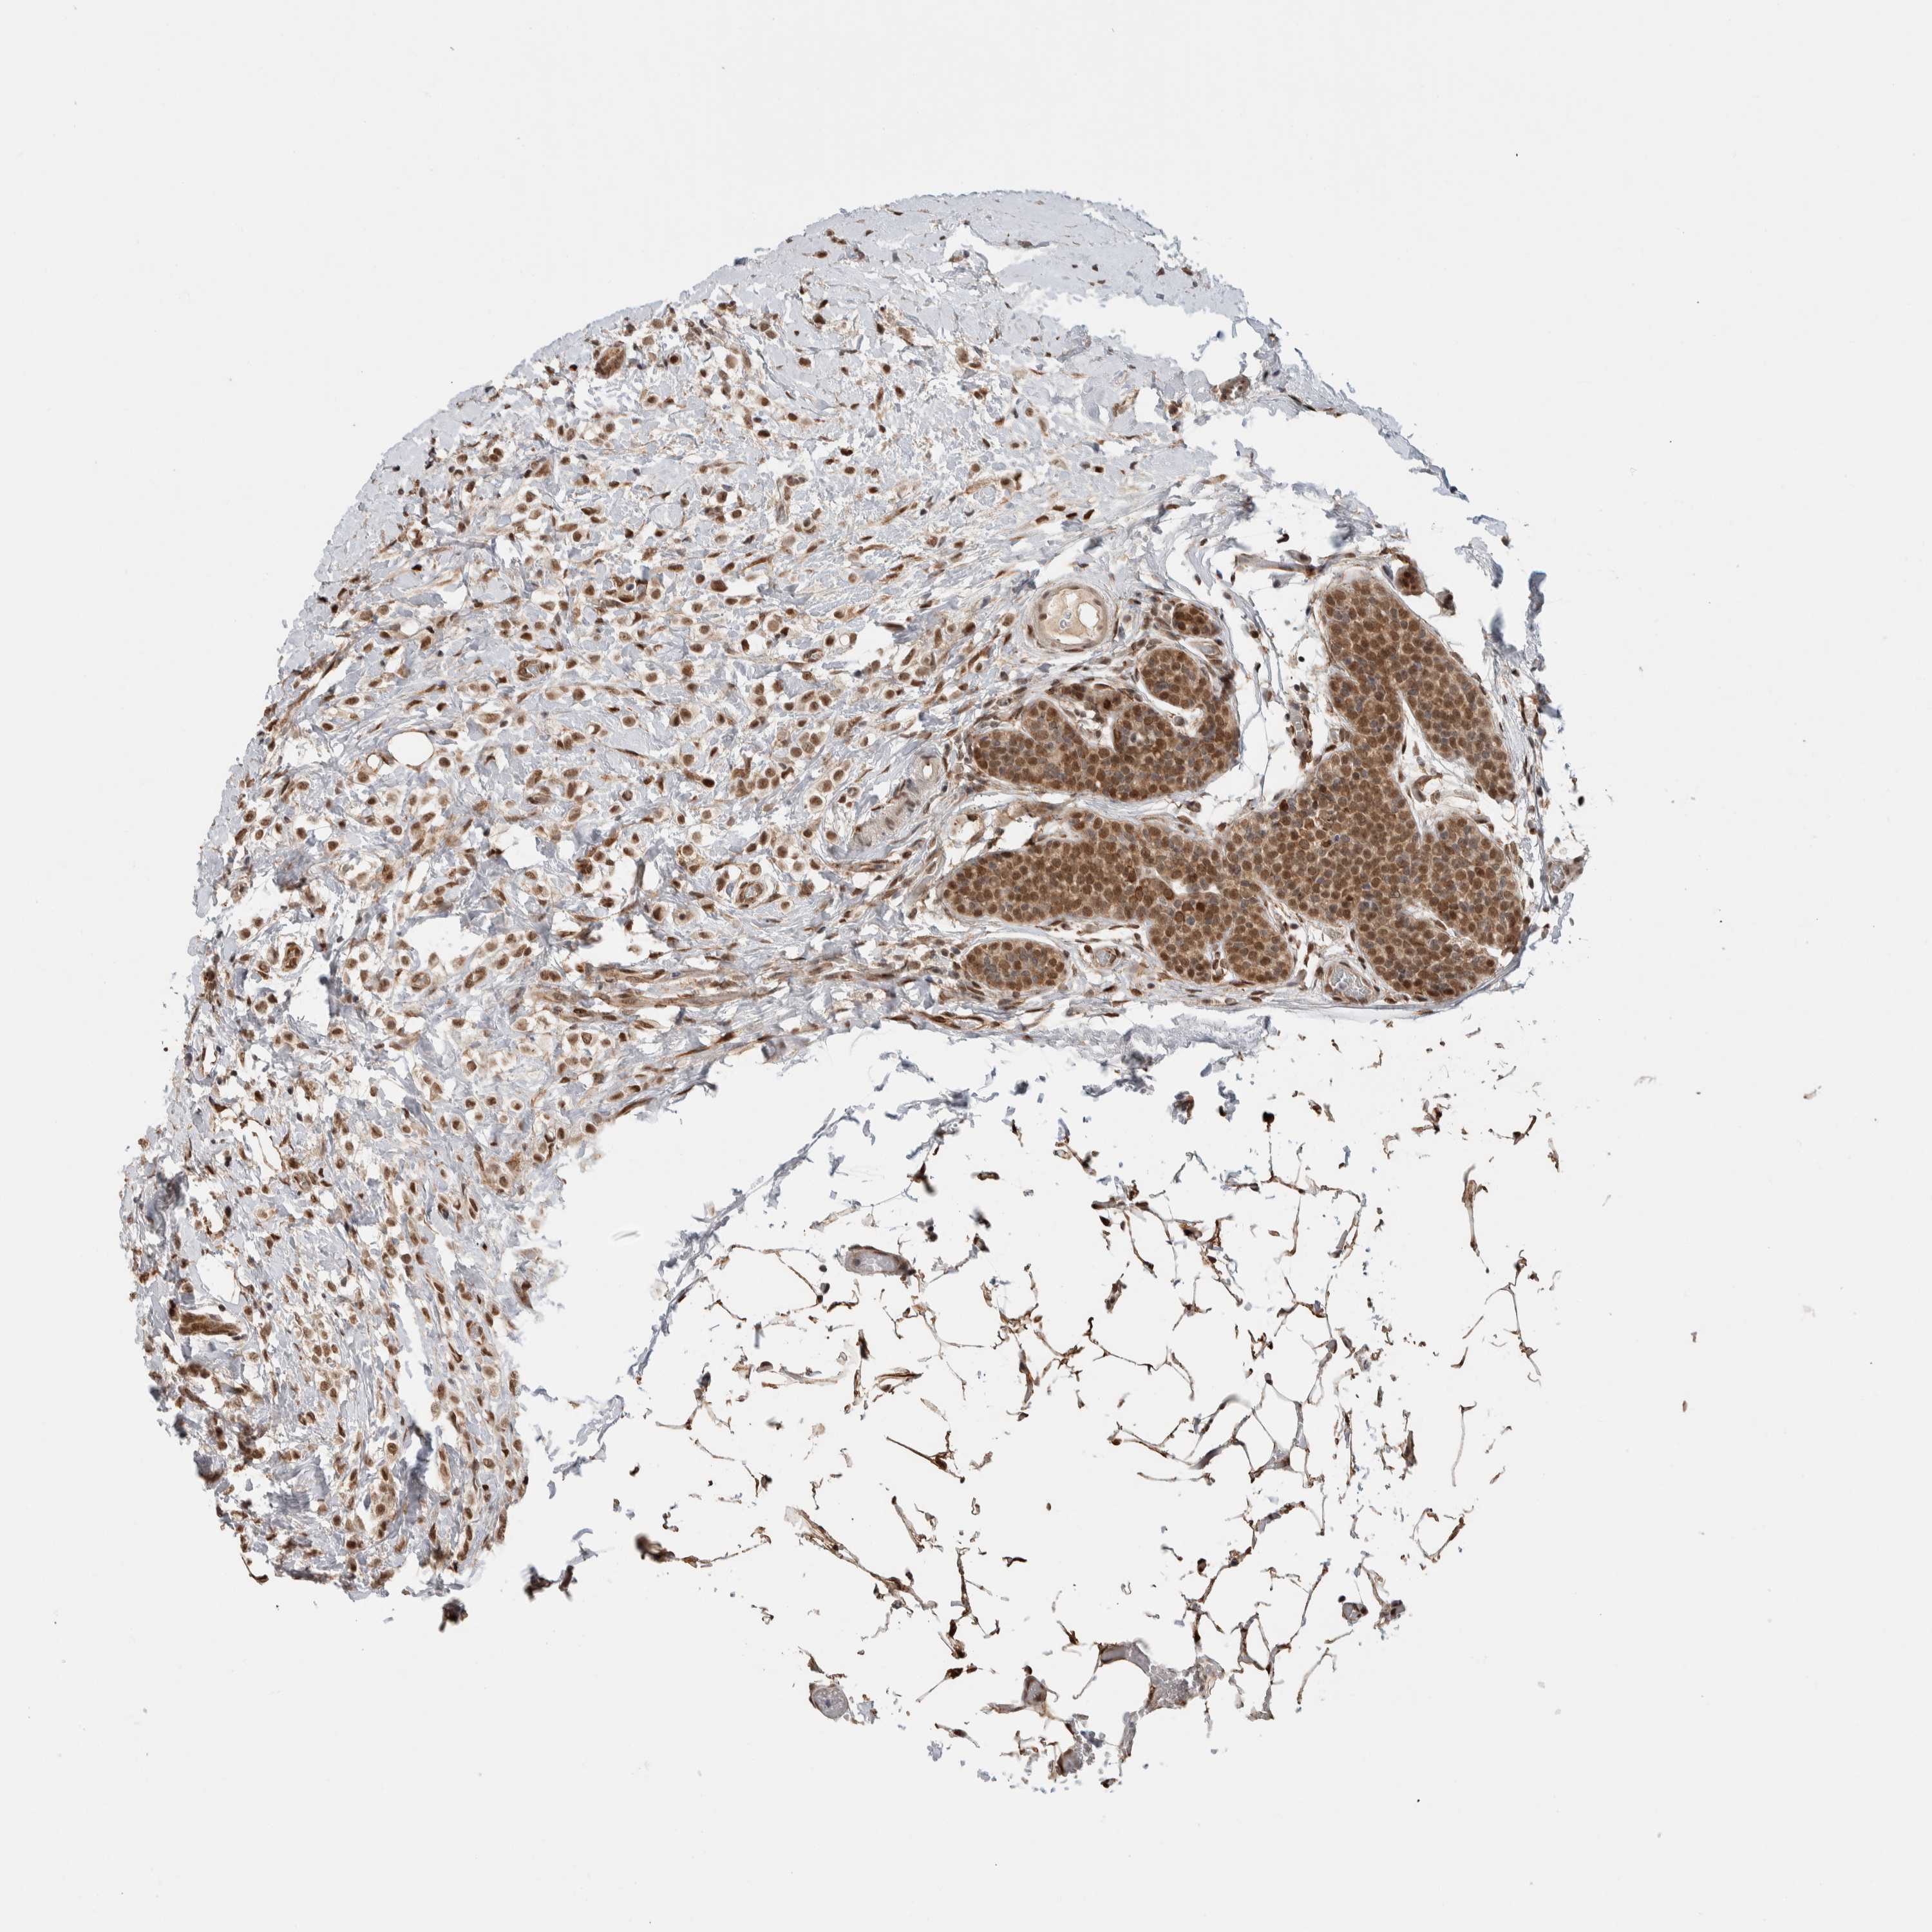

CANCER BREAST CANCER Show tissue menu

BRCA TCGA BRCA VALIDATION PROTEIN EXPRESSION